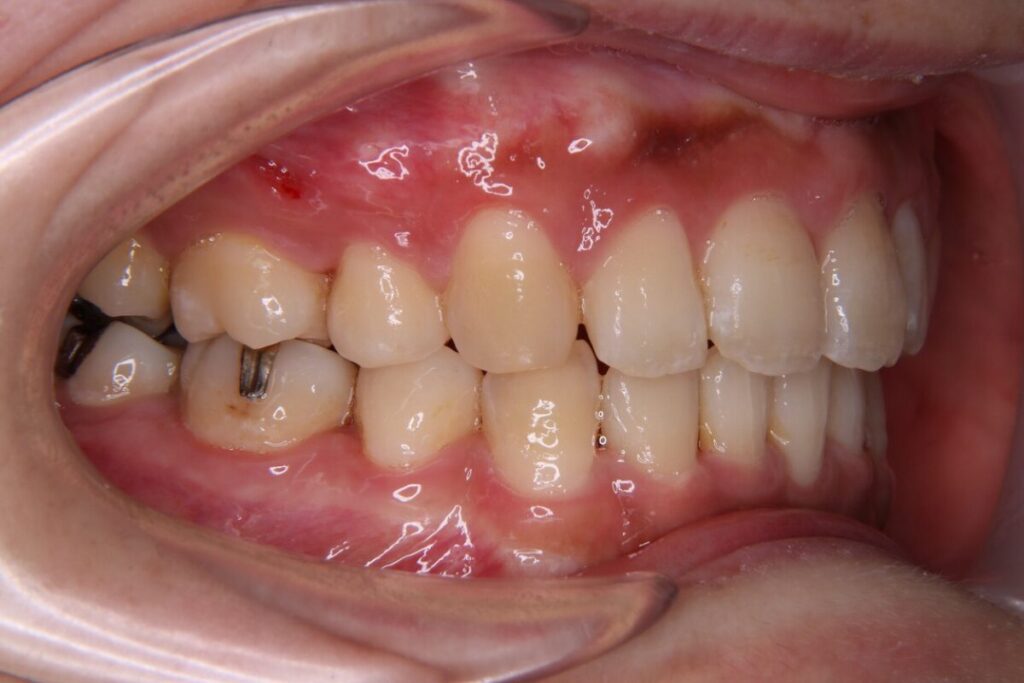

30代女性|過蓋咬合を非抜歯・インビザラインで改善(2年4か月・820,800円)

かみ合わせが深くガミーを気にされ、相談にいらっしゃいました。叢生が中等度にみられましたが、抜歯を避けて歯列全体のアーチを整える方針を選択。

深いかみ合わせでも、本症例のようにマウスピース型矯正装置が適応になることもあります。治療期間は2年4ヶ月で、機能と見た目の両面で整い、歯磨きのしやすさや清潔感も実感されていました。

一歩踏み出した分だけ、生活の快適さが広がる治療でした。